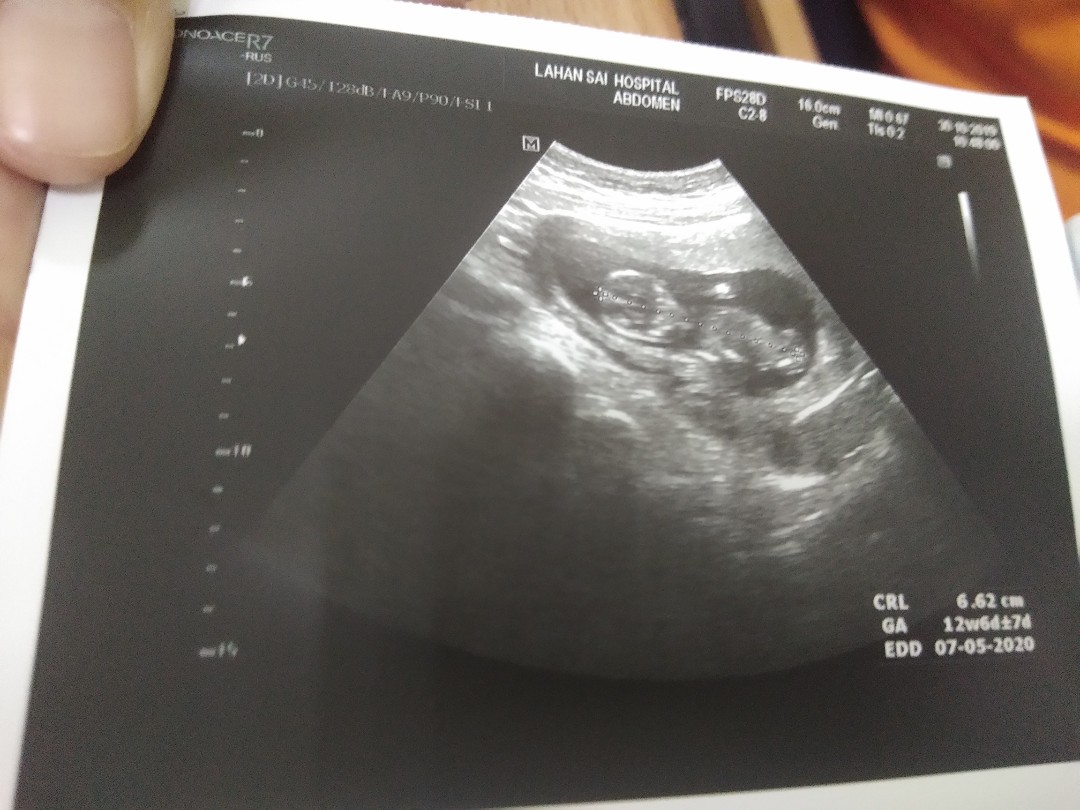

12วีค แต่ตอนนี้17+2 ค่ะ